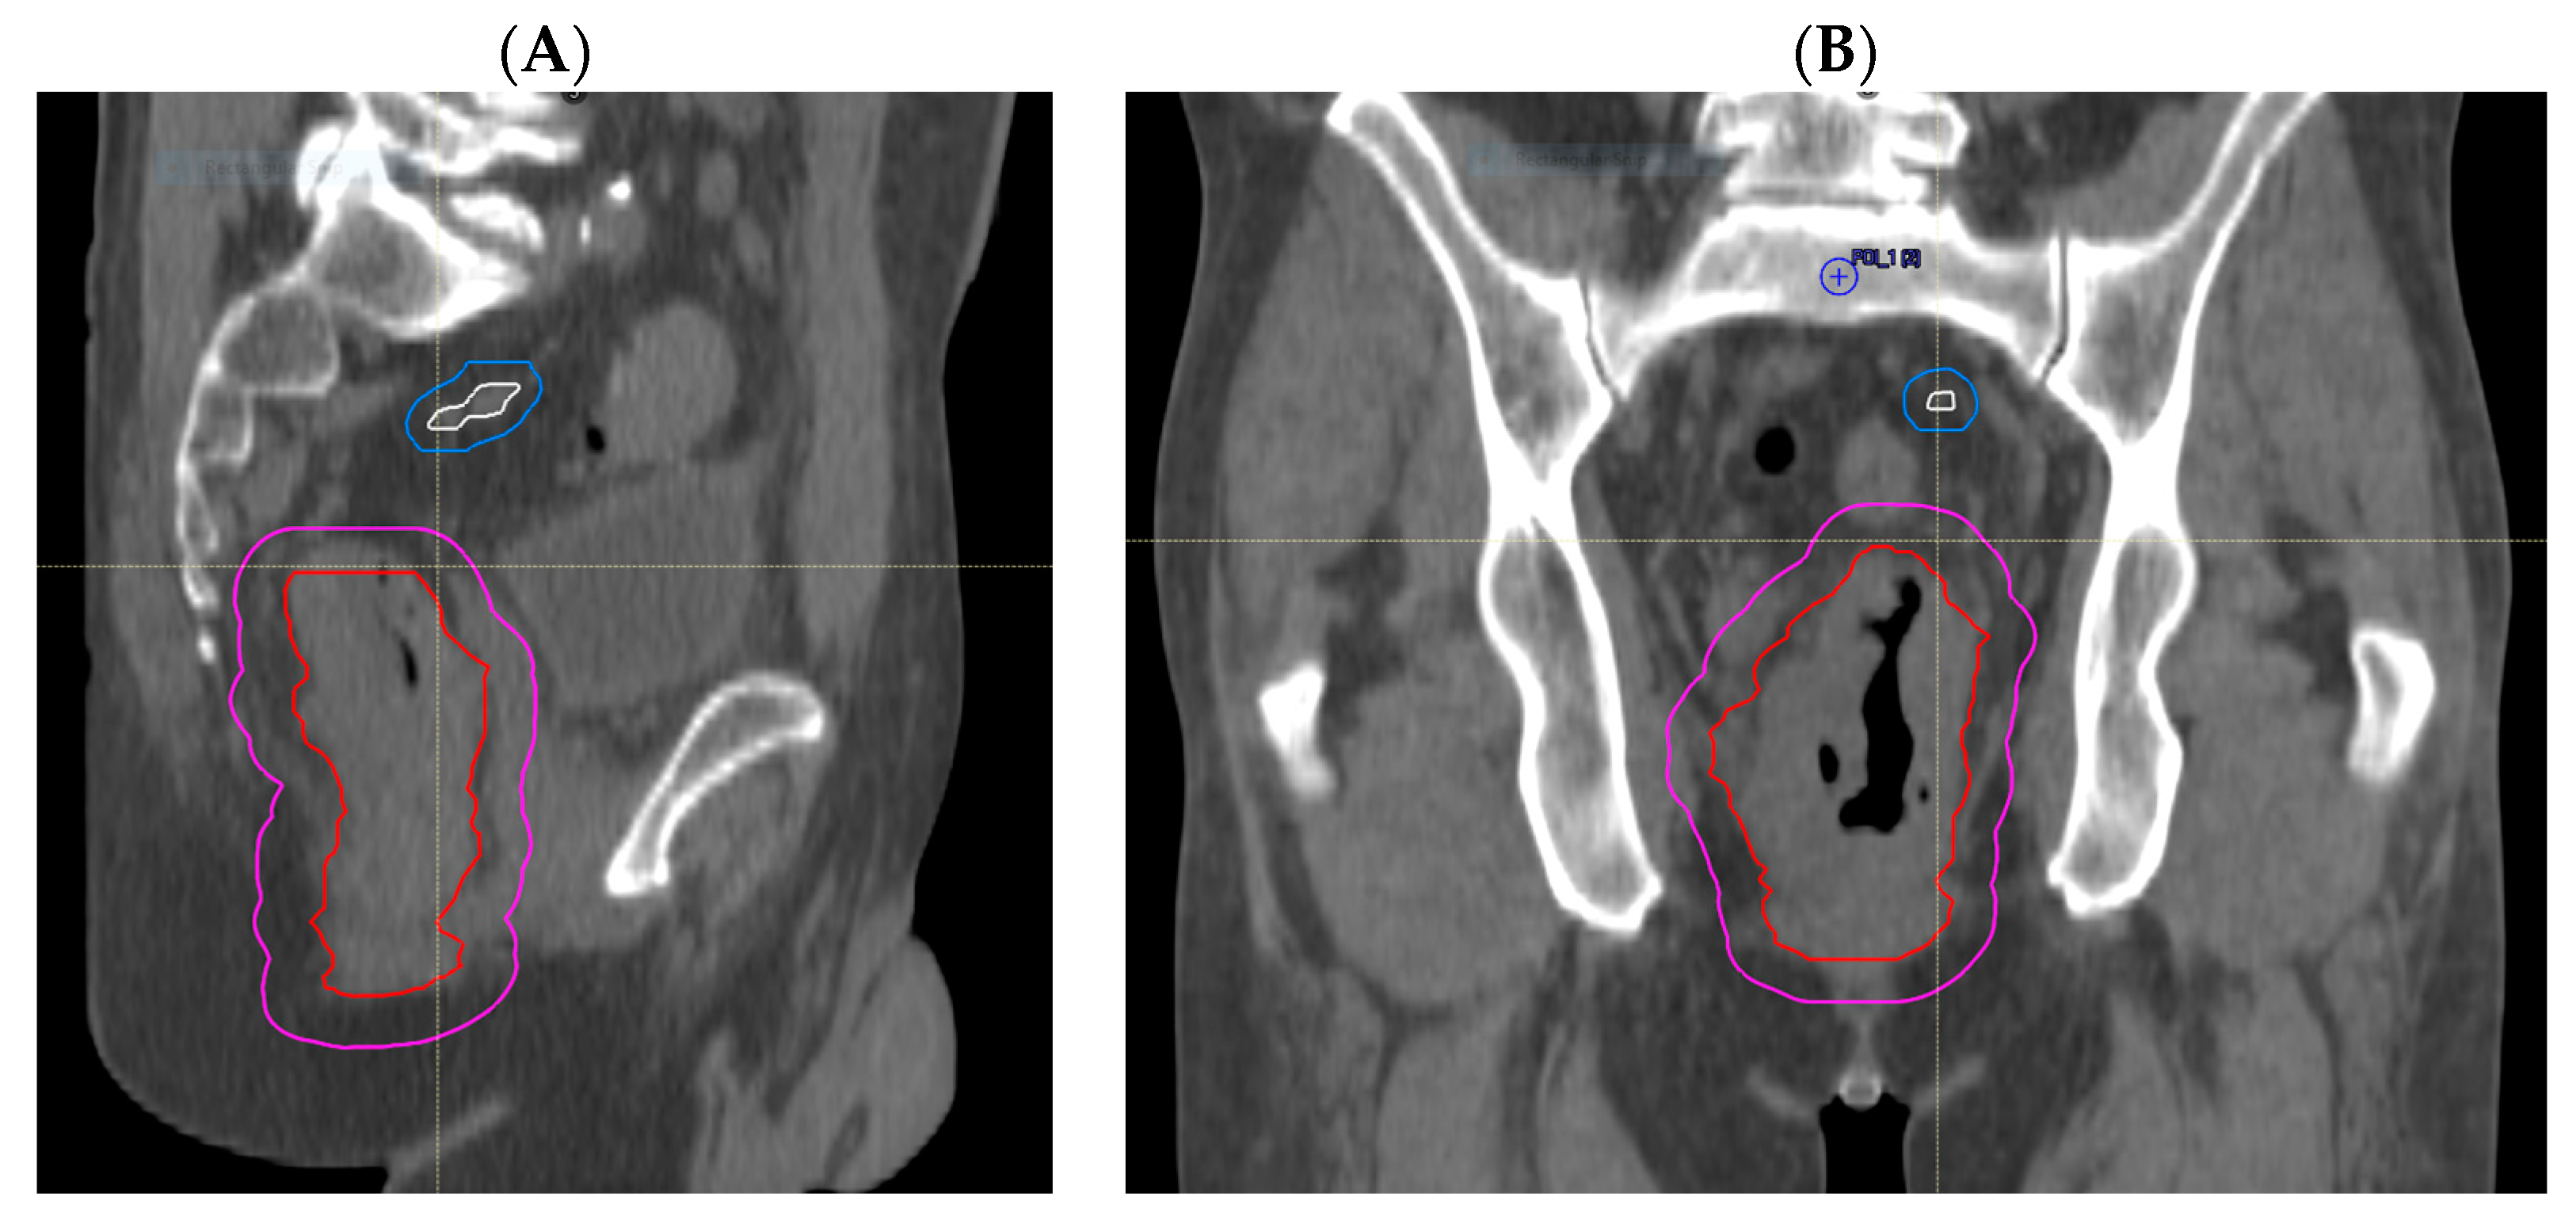

Through treatment volume comparisons, we observed no GTV geographical miss in any of the primary tumours that were all adequately encompassed. However, we observed that delineation of involved lymph nodes and areas of EMVI was more likely to represent sources of uncertainty. Nodal GTV geographical miss in the high-dose boost volume was evident in 5 out of 27 patients (19%); of these, 4 cases (15%) had missed mesorectal nodes that were encompassed in the PTV45Gy, but one node involving the pelvic side wall was outside of the treatment volume in the remaining patient (Figure 2A,B). EMVI GTV geographical miss occurred in 2 out of 27 (7%) patients (Figure 3A,B). These areas of EMVI were both encompassed in the PTV45Gy. Taken together, these results show proof of concept that an adjustment of MRI reporting to highlight the exact extent and location of macroscopic disease, in particular nodal involvement and EMVI, has the potential to improve the accuracy of radiotherapy volume delineation.

Figure 2.

Radiotherapy planning CT showing nodal GTV geographical miss. (A) Sagittal view and (B) coronal view showing nodal disease (white), with its corrected CTV (blue) extending to the right pelvic sidewall, which is not encompassed by the treated CTV (magenta), with GTVp (red) as shown.